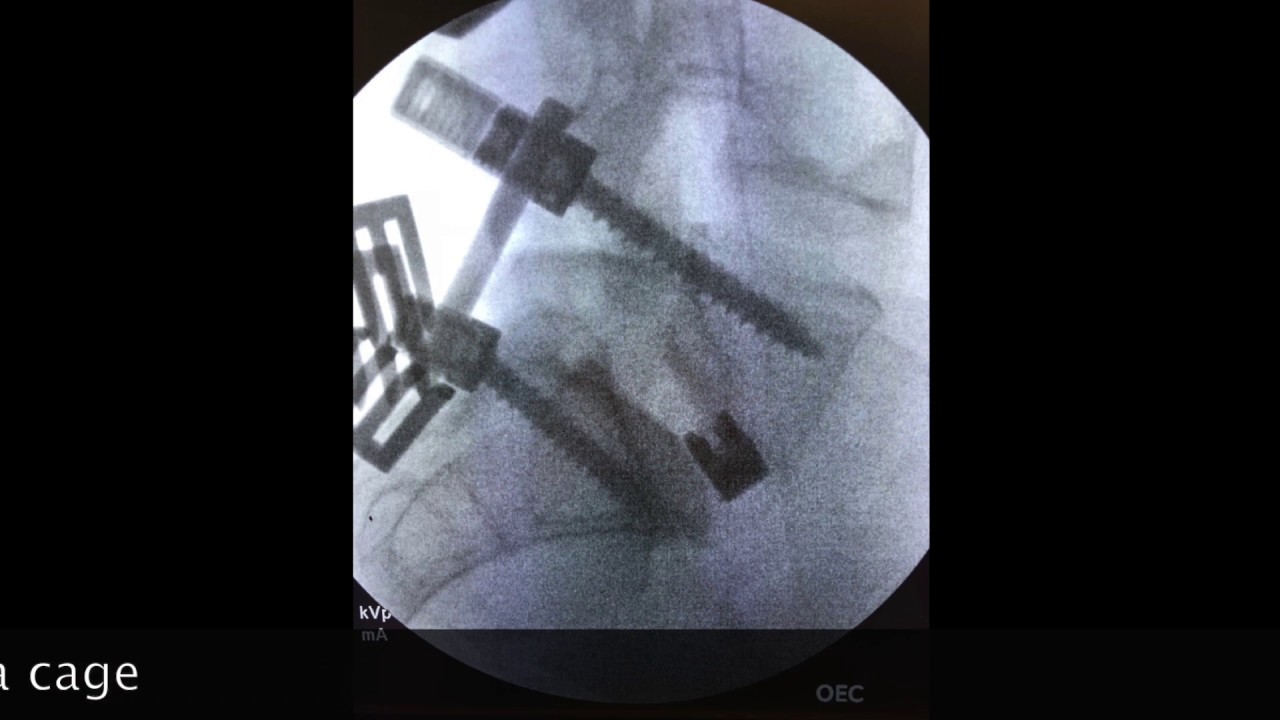

Foto e video